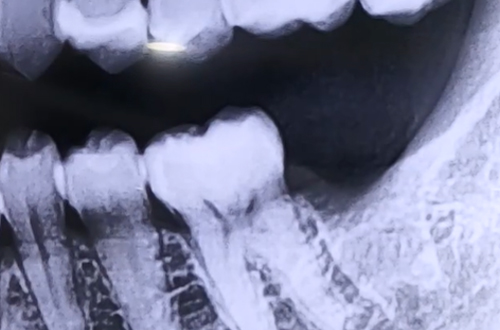

BEFORE

어금니 임플란트를 위해 내원해 주신 환자분이십니다.

해당 환자분의 경우 임플란트 식립 위치와 하치조 신경이 가까우셨는데요.

어금니 임플란트 진행 시에는 그 아래쪽을 지나가는 하치조 신경의 위치를 정확하게 체크하여, 신경에 닿지 않게 하는 것이 매우 중요합니다.

따라서 CT 촬영을 통해 신경의 위치와 신경까지의 거리를 파악한 뒤 그에 맞는 길이의 임플란트를 사용하여 치료를 진행해야 합니다.